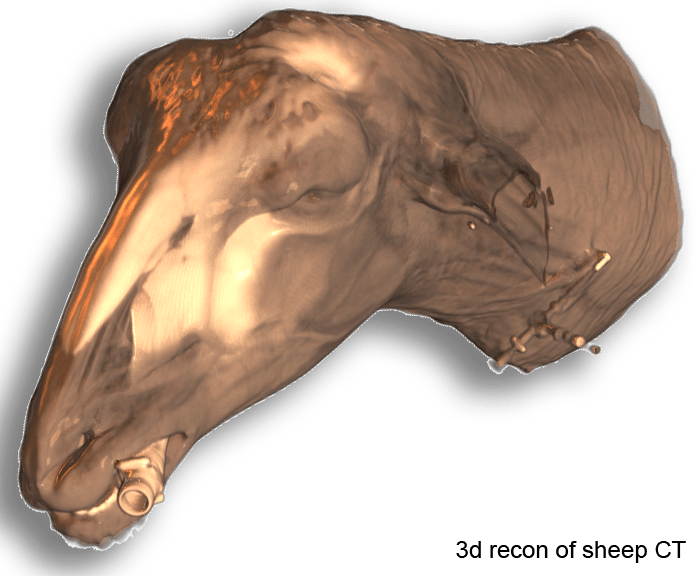

We proudly present atlases, templates, probabalistic tissue maps from sheep and dog to enable quantitative analysis of MRI datasets. The data were tested appropriately with SPM(8/12), but may work also with other software such as FSL.